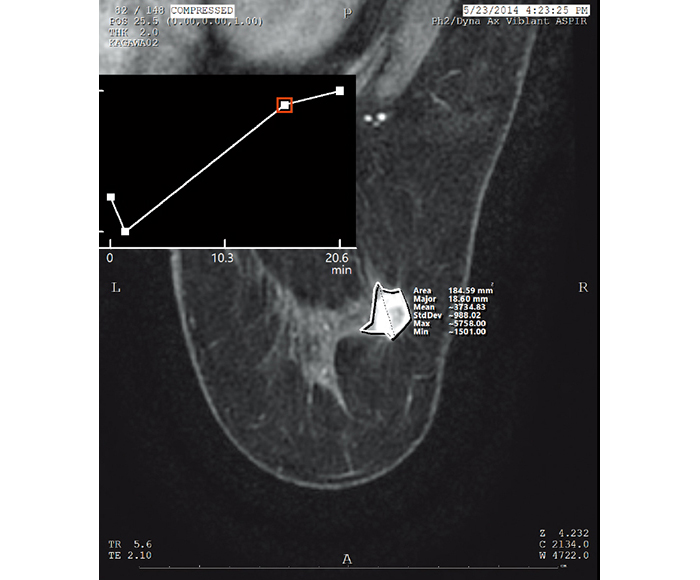

Values for ROI and X-ray gauging can be obtained from the information in each imaging modality.

Time intensity curve